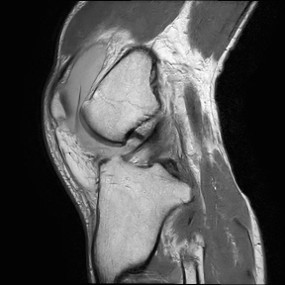

■第3の切り札『プロトン密度強調画像』

T1、T2に次いで重要なのが「プロトン密度強調画像」です。

これは単純に「水(水素)がどれくらい含まれているか」を反映します。

特に整形外科の領域で大活躍しており、膝の半月板や関節の軟骨、靭帯の細かい損傷を見るコントラストに優れています。

スポーツ障害の診断などには欠かせない画像です。

臨床での使いどころ:関節・半月板の評価、脱髄疾患の検出など